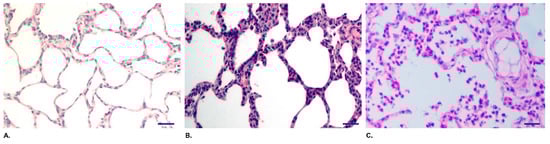

3.3. QH09 Was Safe to Piglets

3.4. QH09 Induced High Levels of Antibodies and Conferred Protection Against Lethal Challenge